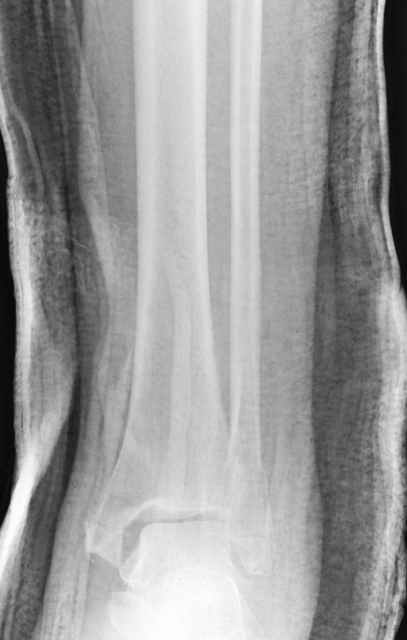

A propos fibular fixation if one is eager to stabilize it separately. In the fracture pattern a way of closed fixation by V-shaped stressed wire (advanced by colleagues from Moscow, prof. Lazarev A.F. et al.) must be excellent. We use indirect closed reduction by the external fixator. Example attached, that fibular fracture is even more suitable for plating but the wire did the job.

Второй случай сделан из одного разреза

Дж